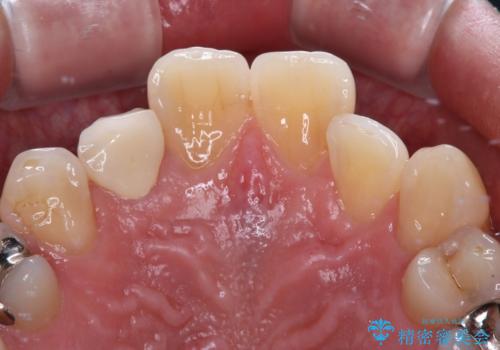

- 内側に倒れている前歯が擦れてしみるとのことで来院された患者様です。

削れていた部分は詰め物が入っていましたが、縁の部分がしみているようで、変色も目立っていたため、オールセラミッククラウンにて補綴治療を行うこととしました。

内側に倒れているため、下顎と強く干渉することが懸念されましたが、無理のない咬み合わせで、形態も左右対称に近い状態で仕上げることができました。